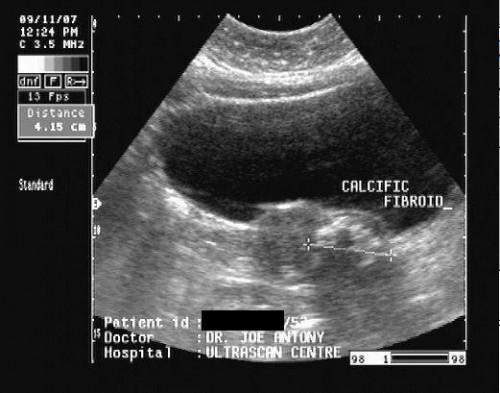

U xơ tử cung bị vôi hóa